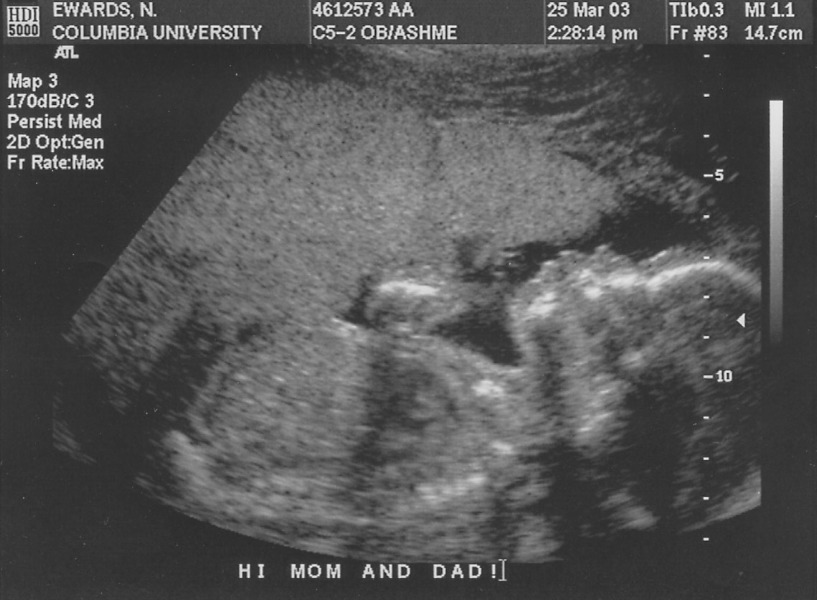

p3250001 Kyle Ultrasound

Approaching human here.